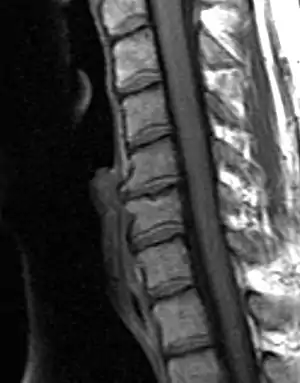

MRI of the lumbar spine, intervertebral disc degeneration